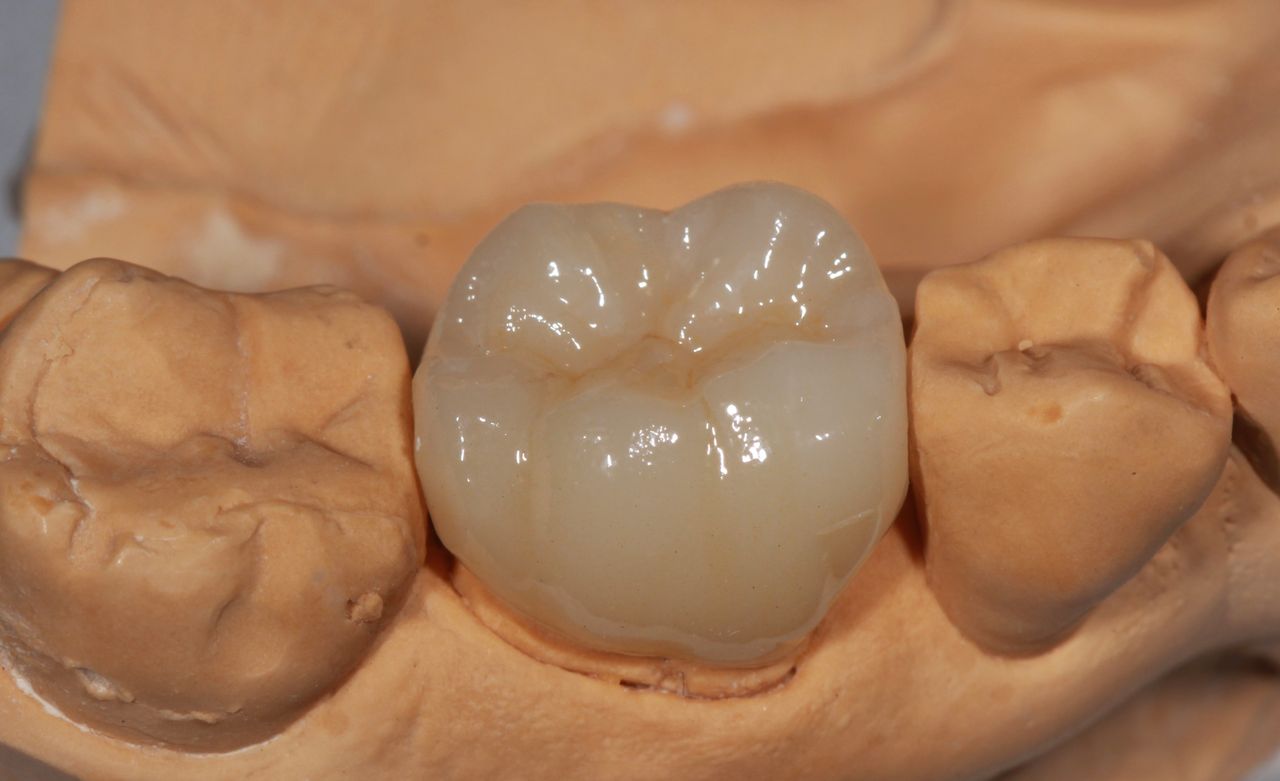

Especialista en prótesis bucal fija y removible, cédula de especialidad 13216976

La especialidad en prótesis Bucal se enfoca en rehabilitar mediante prótesis unitarias, múltiples o totales la función masticatoria de nuestros pacientes brindándoles una mejor estética dental, confort, anatomía dental y función.